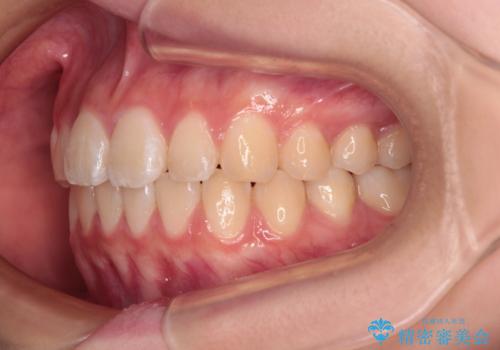

- 上下前歯のねじれを気にして来院された患者様です。

ワイヤー矯正でもマウスピース矯正でも対応可能でしたが、マウスピース矯正の自己管理が面倒であること、上顎前歯の捻転が著しいことから、ワイヤー矯正での治療を希望されました。